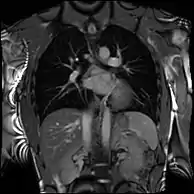

Cardiac magnetic resonance imaging (CMR) is a type of non-invasive medical test using magnetic resonance imaging (MRI) technology to assess the structure and function of the cardiovascular system.[2] It is generally used alongside echocardiography to look at the heart in congenital heart disease and diseases of the heart muscle and valves.[2] It can detect diseases of the aorta such as dissection, aneurysm and coarctation, and can be used to assess diseased blood vessels of the heart and of the lungs.[2]

Cardiovascular MRI is complementary to other imaging techniques, such as echocardiography, cardiac CT, and nuclear medicine. The technique has a key role in evidence-based diagnostic and therapeutic pathways in cardiovascular disease.[3] Its applications include assessment of myocardial ischemia and viability, cardiomyopathies, myocarditis, iron overload, vascular diseases, and congenital heart disease.[4] It is the reference standard for the assessment of cardiac structure and function,[5] and is valuable for diagnosis and surgical planning in complex congenital heart disease.[6]

Congenital heart defects are the most common type of major birth defect. Accurate diagnosis is essential for the development of appropriate treatment plans. CMR can provide comprehensive information about the nature of congenital hearts defects in a safe fashion without using x-rays or entering the body. It is rarely used as the first or sole diagnostic test for congenital heart disease.

Rather, it is typically used in concert with other diagnostic techniques. In general, the clinical reasons for a CMR examination fall into one or more of the following categories: (1) when echocardiography (cardiac ultrasound) cannot provide sufficient diagnostic information, (2) as an alternative to diagnostic cardiac catheterization which involve risks including x-ray radiation exposure, (3) to obtain diagnostic information for which CMR offers unique advantages such as blood flow measurement or identification of cardiac masses, and (4) when clinical assessment and other diagnostic tests are inconsistent. Examples of conditions in which CMR is often used include tetralogy of Fallot, transposition of the great arteries, coarctation of the aorta, single ventricle heart disease, abnormalities of the pulmonary veins, atrial septal defect, connective tissue diseases such as Marfan syndrome, vascular rings, abnormal origins of the coronary arteries, and cardiac tumors.